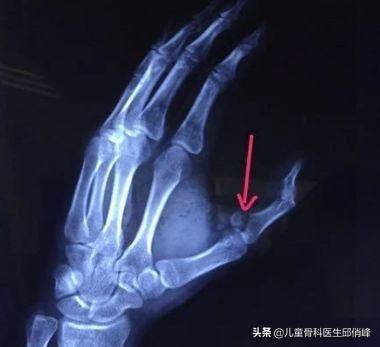

大拇指骨折了,已3个月了,怎样恢复?

骨折完全愈合了?没有畸形愈合?当初骨折有没有涉及关节的情况?有没有规范治疗?是保守治疗还是手术治疗?治疗过程中有没有其他并发症?

假设骨折复位良好,没有涉及关节,3个月也一般都已经愈合了,愈合后没有畸形,也没有伤口,治疗过程中一切顺利。一般会留下手指关节臃肿,僵硬的情况,只要每天进行功能锻炼,可以被动+主动,被动活动也就是另一只手帮忙掰手指,活动关节,每天四五次,一次十分钟。被动活动结束开始主动活动,就是让手指自己活动,另一只手不帮忙。